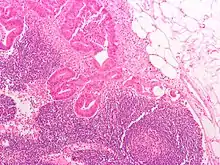

Histology of a normal lymphoid follicle, showing dark, light, mantle and marginal zones.

A lymph node is divided into compartments called nodules (or lobules), each consisting of a region of cortex with combined follicle B cells, a paracortex of T cells, and a part of the nodule in the medulla.[15] The substance of a lymph node is divided into the outer cortex and the inner medulla.[3] The cortex of a lymph node is the outer portion of the node, underneath the capsule and the subcapsular sinus.[15] It has an outer part and a deeper part known as the paracortex.[15] The outer cortex consists of groups of mainly inactivated B cells called follicles.[4] When activated, these may develop into what is called a germinal centre.[4] The deeper paracortex mainly consists of the T cells.[4] Here the T-cells mainly interact with dendritic cells, and the reticular network is dense.[16]